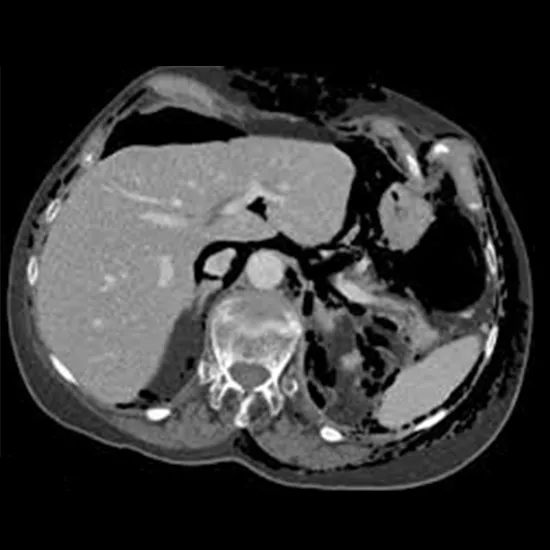

CECT Upper Abdomen is a contrast study of the upper abdomen used to visualise the internal organs and their disease state.

An abdominal CT scan takes pictures of the liver, spleen, kidneys, bladder, stomach, intestines, pancreas, and adrenal glands, blood vessels, and lymph nodes

using a special X-ray machine.